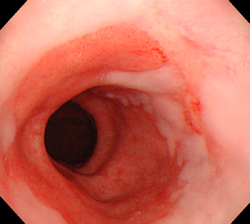

- Özofajit yapmış: Burada endoskopi esnasında yemek borusunda çeşitli derecelerde hasar tespit edilir. Hastaların %50 si de bu klasmandadır. Hasarın derecesine göre kendi içinde 4 dereceye ayrılır: